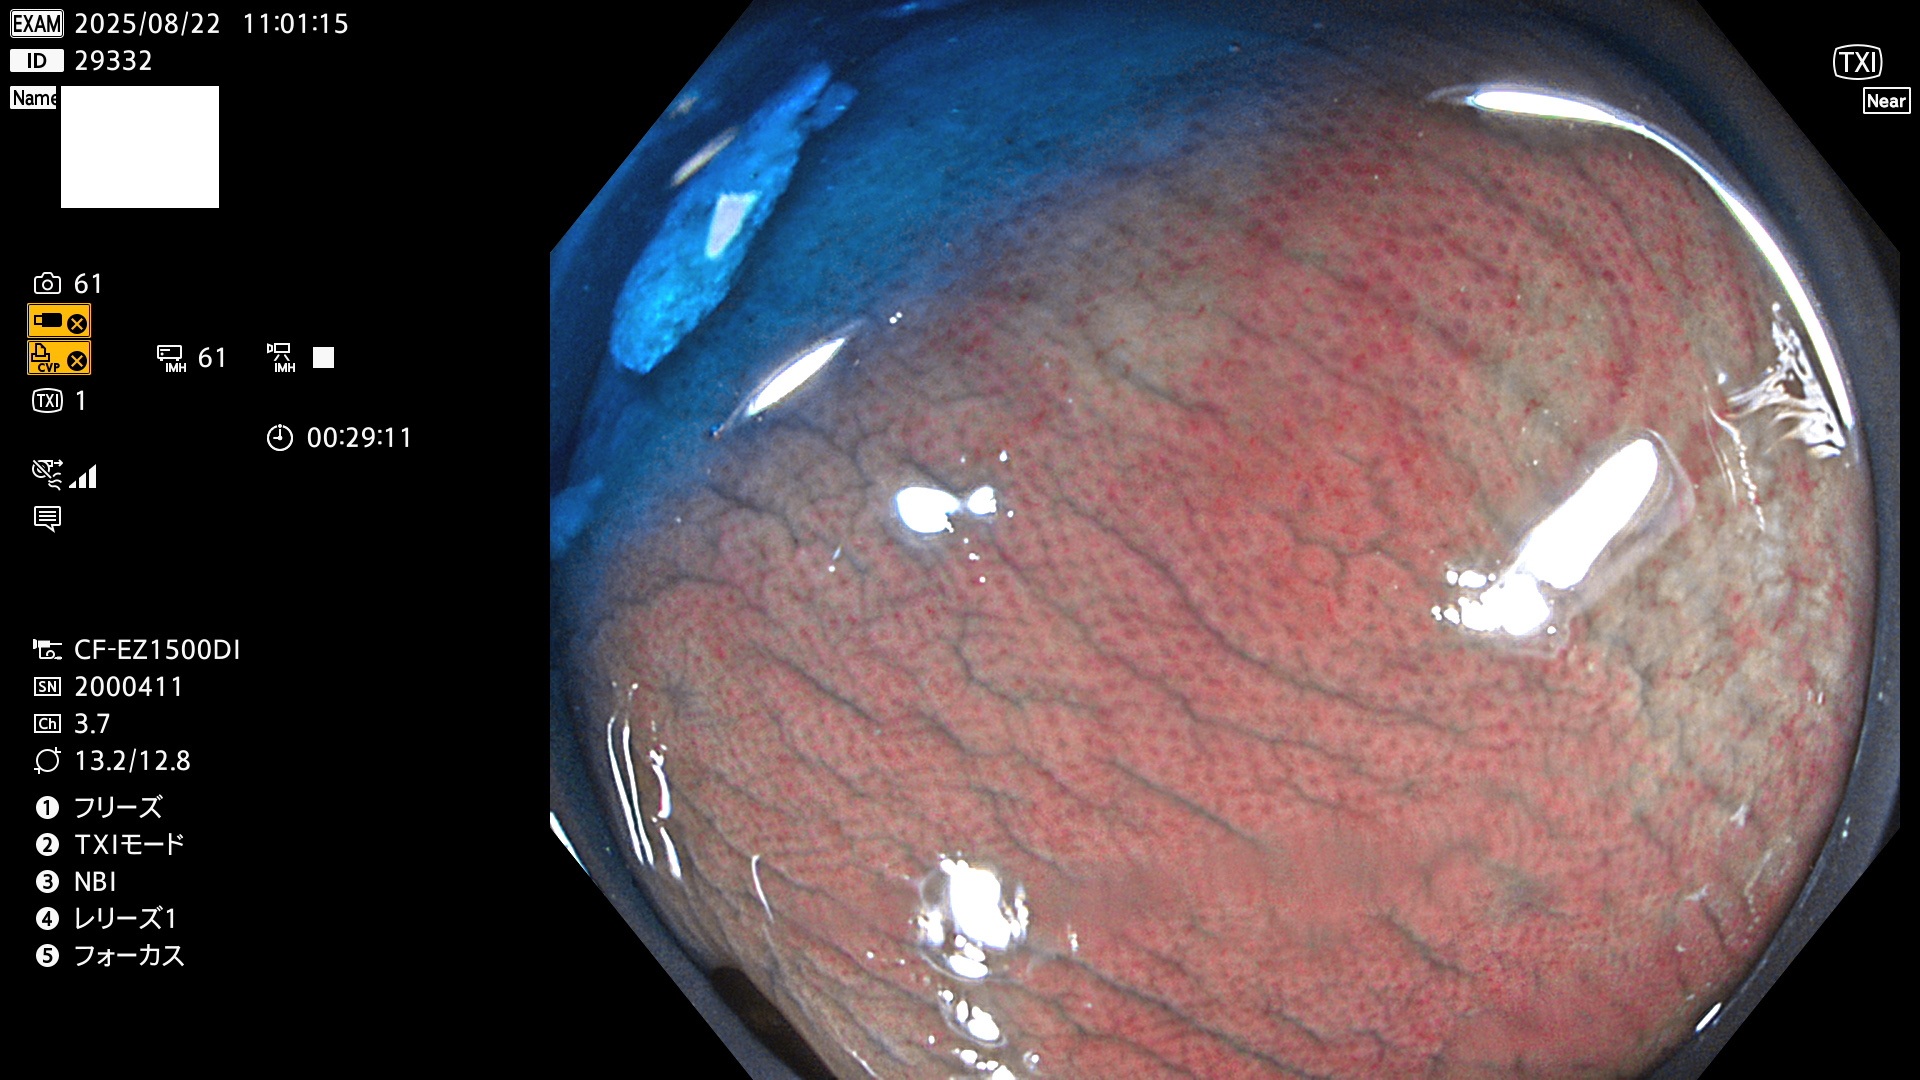

完全に平坦な物をUb、陥凹している物をUcと呼びます。Ubは認識が困難で、Ucはびらん(炎症)と紛らわしいために見落とされやすく、「内視鏡後・大腸癌」の原因になります。

毎週の検査(木・金・土・日)に発見されたUbとUc型・腺腫を、その週の日曜の夜にUPし1週間、提示します。

2025年8月21日〜8月24日の4日間(30件)5個 (Uc_ADR=3個/35人=14%)